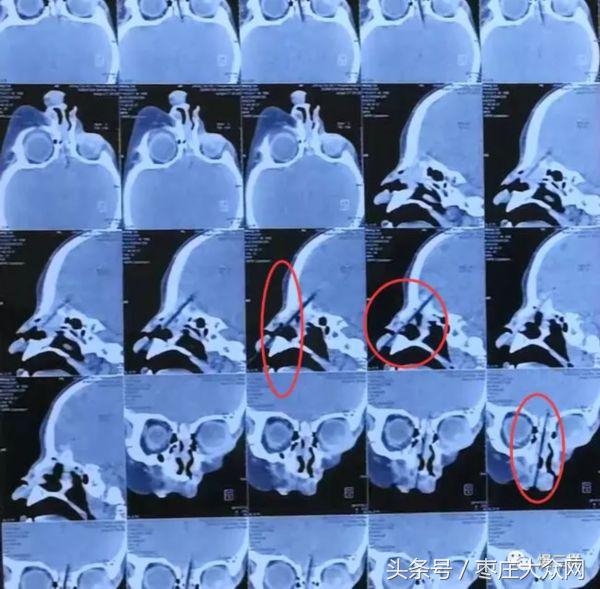

记者了解到,8月4日下午3点左右,这名男童跟着家长吃串,将吃串剩下的竹签叼在嘴里玩。家长一时分神,嘴里含着竹签的男童不慎跌倒,竹签从口腔前牙区前庭沟直接插入鼻腔,经筛窦刺入颅内,进入颅内的竹签长度是1.5~2CM。万幸的是,竹签从男童两个眼眶中间穿过,并未伤到眼球。

刘超说,好在竹签没有断裂,万一竹签断裂在颅内,就要进行开颅手术。为了应对特殊情况,当晚参与会诊和应对突发情况的有3名口腔外科的医生、2名麻醉医生、1名眼科医生、1名耳鼻喉科医生、1名神经外科医生以及2名护理。手术后12小时,院方对患儿复查了脑CT,未发现颅脑内有积液、积气等感染情况。目前男童整体状态较稳定,但仍有出现颅内感染和脑脊液瘘的可能性,一旦出现这种情况,将会进行二次手术。院方将会观察至少一周的时间,如恢复顺利,一周左右即可出院。